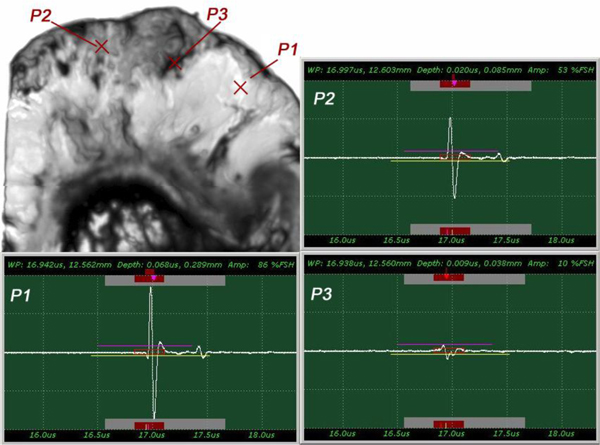

The insertion technique [75] is used to measure the acoustic properties of the different materials. This technique is a relative method, which employs water as the reference to measure the transmission of longitudinal ultrasonic waves through solid media embedded in an aqueous environment (i.e., water). Therefore, the waveform of the wave reflected from the substrate via water was taken as a reference waveform (Fig. 16). In this case, the acoustic beam is focused on the sapphire substrate, and because of the high reflectivity, the reflected signal carries relatively high energy and its waveform has the amplitude of 100% Full-Screen Height (hereinafter called simply “FSH”). The echo amplitudes represent the product of the local scattering strength and the attenuation loss factor, which takes into account scattering in all directions and absorption. Based on the difference, in contrast, three points (i.e., P1, P2 and P3 in Fig. 17) were chosen. The waveforms corresponding to these points are shown in Fig. (17), and their amplitudes of waveforms are shown in Table 2.

| P1 | A = 86% FSH |

| P2 | A = 53% FSH |

| P3 | A = 10% FSH |

The tissue (see Fig. 17) includes melanoma cancer cells, which were sandwiched between the poly-silicone cover and the sapphire substrate.